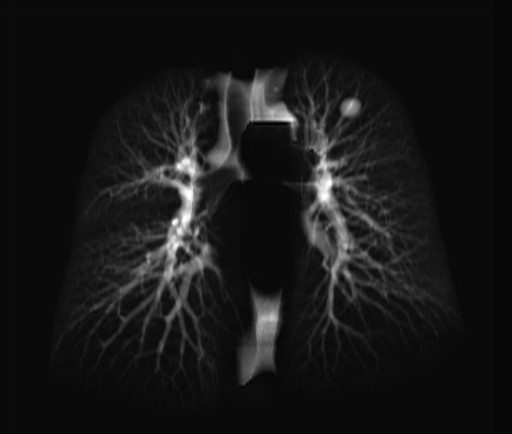

In contrast to 2D masks usually employed in the process of training 2D lung field segmentation algorithms [8], the masks generated by our method reflect the exact position the of lungs in the image even when occluded by other structures. As a result, the subdiaphagramatic and retrocardiac areas which are known as hidden spots for nodule detection [2] are included in the mask. An example of a 3D mask and a 2D mask is given in Fig. 3

Refer to caption

(a)

(b)

Figure 3: (a) 3D Lung segmentation Mask (b) 2D Projection of the Lung Mask